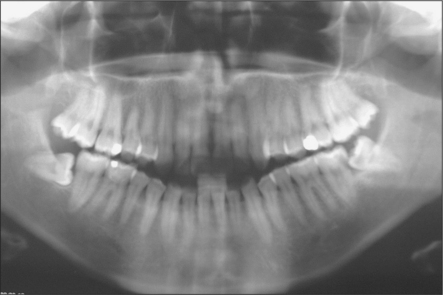

Extraction is indicated if the tooth is erupted and causing trauma to the cheek or operculum overlying the lower wisdom tooth. Unerupted third molars are often asymptomatic and unless there is associated pathology (Fig. 5.20) they should be left, regardless of whether the lower third molars are to be removed under general anaesthesia.

image

Fig. 5.20 Bad taste associated with unerupted upper third molar. Little radiographic (a) or clinical evidence for the large dentigerous cyst (b) removed with the wisdom tooth.